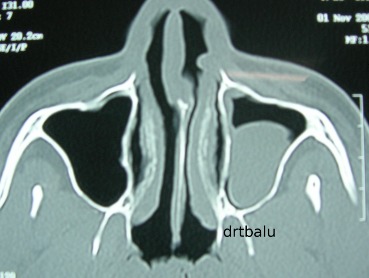

Axial CT PNS showing maxillary antral cyst

Polyp arising from the maxillary sinus – is usually solitary. It exits the antrum via the natural / accessory ostium. This causes an enlargement of ostia. Radiologically it appears like a dumbbell because of the constriction present in the midline (ostial exit point). In these patients the medial wall of the maxillary sinus bows into the nasal cavity. This can be clearly visualised in the CT scan images. Obstruction caused by this polyp to the drainage channels of ethmoidal and frontal sinuses (middle meatus) can cause opacification of those sinuses also there by making it difficult to identify the exact origin of the nasal polyp. In this scenario the bone remodelling that takes place in the medial wall of maxillary sinus could be the clincher. If these polyp passes posteriorly to exit via the choana it could be clearly visualized in the axial cuts taken at the choanal level.